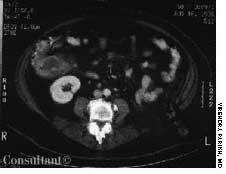

A 13-year-old girl who had leukemia presented to the emergency department with fever; chills; weight loss; fatigue; and a painful, erythematous rash with a central black lesion on the upper thigh. The patient was neutropenic and had been undergoing chemotherapy for 1 week.